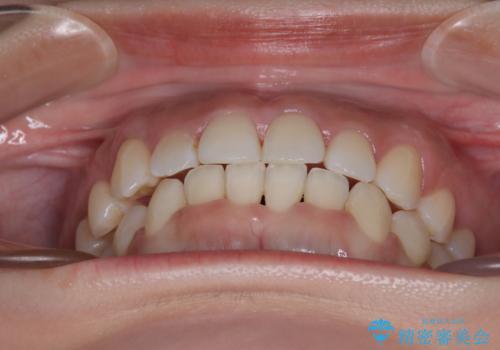

- 上下前歯のデコボコを気にして来院された患者様です。

上顎歯列が下顎の歯列に対して狭小であり、一部下顎の奥歯が上顎よりも外側に位置している状態でした。